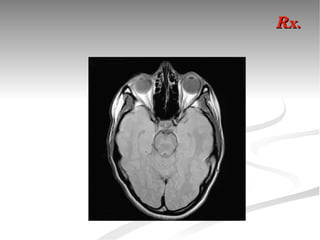

Rx.